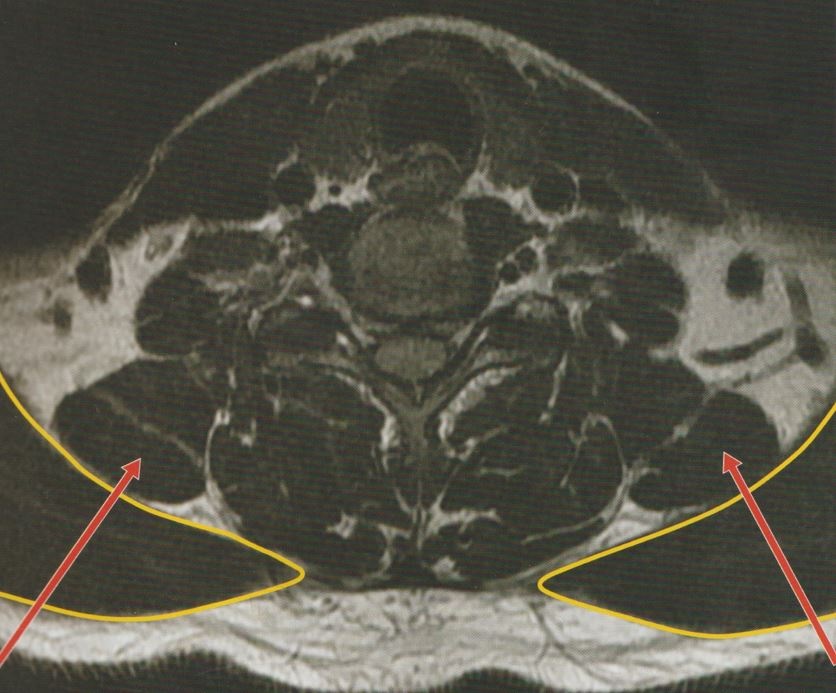

경추 7번 레벨에서 도침치료를 진행할 때의 진입 방향입니다.

이 방향으로 침을 놓으면, 단순히 승모근뿐 아니라 승모근 아래에 위치한 여러 근육까지 동시에 치료할 수 있어 치료 효과를 높일 수 있습니다.

승모근뿐 아니라 사각근, 흉쇄유돌근, 두반극근, 경반극근 등 통증이 발생한 근육의 포인트를 찾아 치료를 진행하면 치료 효과를 더욱 높일 수 있습니다.